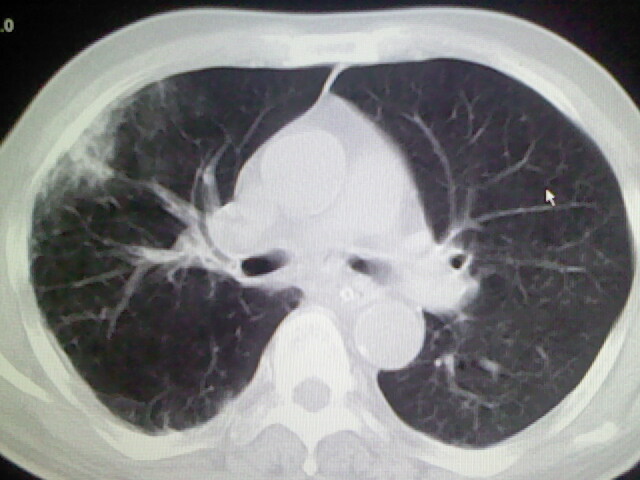

男,70岁,脑出血,长期卧床,左侧背部可触及肿块

右肺病灶考虑炎症性。

右肺病灶考虑炎症性

考虑右肺及左肺下叶炎症。

右肺及左肺下叶炎症。

考虑右肺及左肺下叶慢性炎症。

右侧肺部见片状密度增高影,边缘模糊。考虑炎症。另食管壁增厚。

右肺上叶前段病呈楔形,其尖端指向肺门,考虑肺动脉栓塞可能性大.